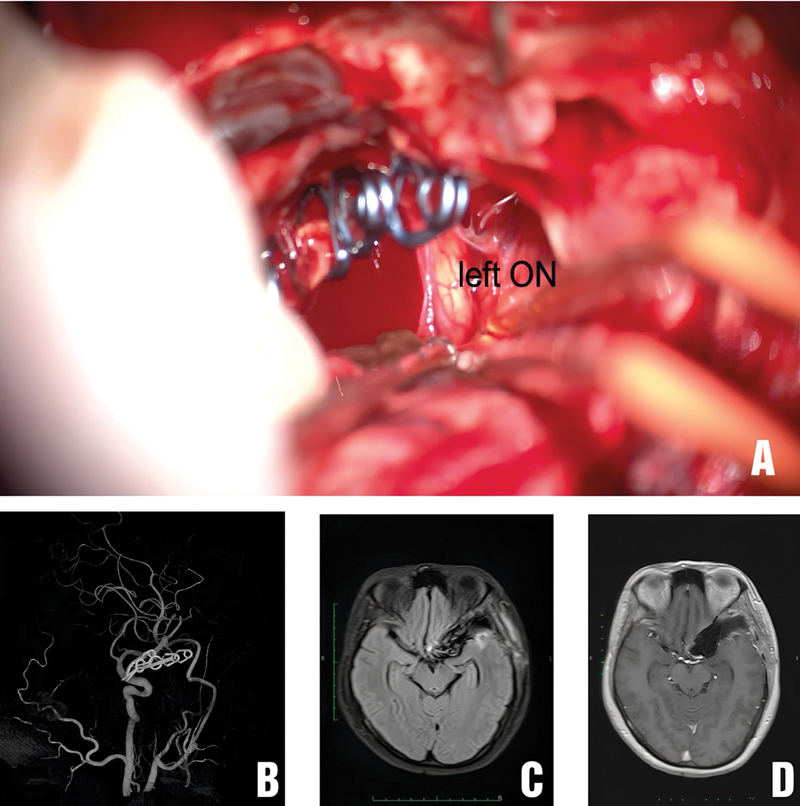

Flow diverter (FD) is often the first-line treatment for giant internal carotid artery aneurysms, with a high rate of aneurysm occlusion. However, up to 10% of giant cerebral aneurysms increase in size after FD treatment. Surgery is usually considered if the giant internal carotid artery aneurysm continues to enlarge and cause compression. We report a case of a giant internal carotid artery aneurysm that continued to increase in size after FD treatment and was subsequently treated surgically. We also review the literature on the management of giant cerebral aneurysms that increased in size after FD. A 41-year-old female patient was diagnosed with a right giant internal carotid artery aneurysm and was initially treated with FD. After FD, the patient's vision in the right eye did not improve. Despite medical treatment, her vision continued to deteriorate. The patient presented at our hospital with reduced vision in both eyes. Magnetic resonance imaging and digital subtraction angiography with balloon test occlusion confirmed the presence of a giant thrombosed aneurysm in the right internal carotid artery, compressing the right optic nerve and optic chiasm. The patient underwent external carotid artery-middle cerebral artery bypass surgery using a radial artery graft, aneurysm sac dissection with thrombus removal, and reconstructive clipping of the aneurysm neck. After surgery, the patient's vision in both eyes improved immediately and did not develop any new neurological symptoms. Extracranial-intracranial arterial reconstructive surgery is a viable option for treating giant internal carotid artery aneurysms that have undergone FD treatment but continue to present with progressive mass effects.